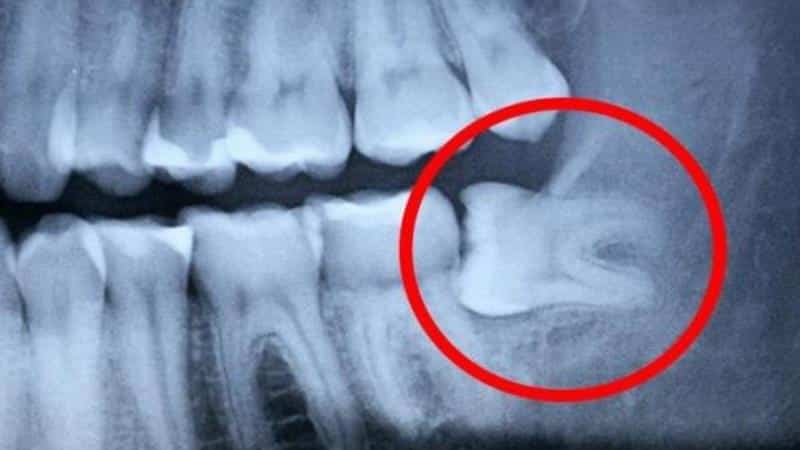

Если у беременной женщины начинает расти зуб мудрости, важно сделать рентген, чтобы врач мог оценить ситуацию.

Вы можете лишь предполагать, что у вас начинается рост зуба мудрости. Окончательный диагноз может установить только врач, основываясь на результатах рентгенографии.